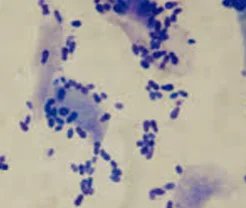

This entails taking samples from the skin’s outer layers, staining them with a special stain, and evaluating them under a microscope for infection, inflammation, tumors, and so on.

This entails taking samples from the ear canal (usually with a cotton swab), rolling the samples on a microscope slide, then heat fixing and staining the samples, and then evaluating the sample under a microscope. The samples can often tell us what type of infection is present in the ear, how to treat infection more effectively and if the infection is resolving or has resolved.